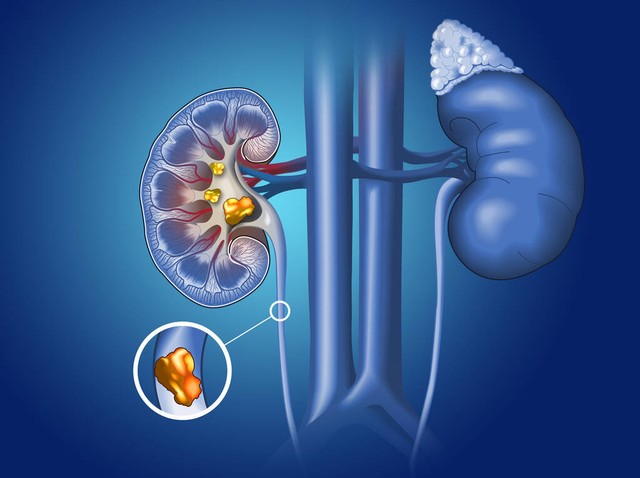

输尿管结石致肾绞痛是泌尿外科最常见的急症。当今,随着临床医学技术的发展,输尿管结石致肾绞痛诊疗技术和诊疗手段随着科学技术的进步也在不断更新发展。

突然发作的肾区剧烈疼痛,大多是由结石滑落入输尿管导致的肾盂或者输尿管平滑肌痉挛,其发病没有任何先兆。典型的表现有阵发性腰痛或沿输尿管走行下腹部疼痛,剧烈难忍,伴恶心呕吐,有血尿或镜下血尿,弯腰屈膝位时可稍减轻;查体肾区叩击痛、输尿管走行梗阻位置压痛明显,且可沿输尿管行径放射至同侧腹股沟,还可涉及同侧*丸睾**或阴唇;结石处输尿管膀胱壁段或输尿管口,可伴有膀胱刺激症及尿道和阴茎头部放射痛。也可伴有尿频、尿急、尿痛、血尿、下坠、畏寒、发热等不适。